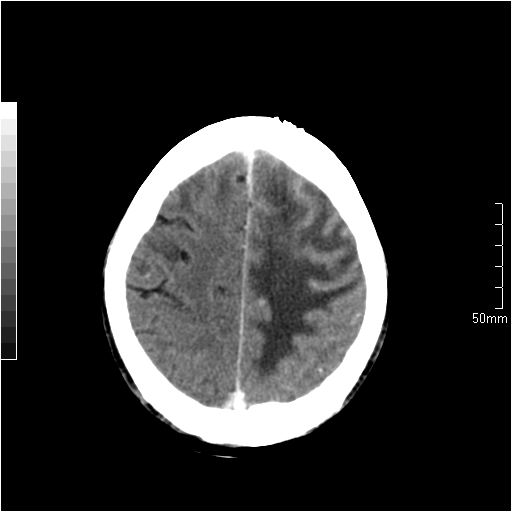

以下是引用天南地北在2007-6-25 12:39:00的发言:[br]有占位效应[br]支持术后复发

以下是引用zjzjr在2007-6-25 12:38:00的发言:[br]左侧复发,右侧转移。